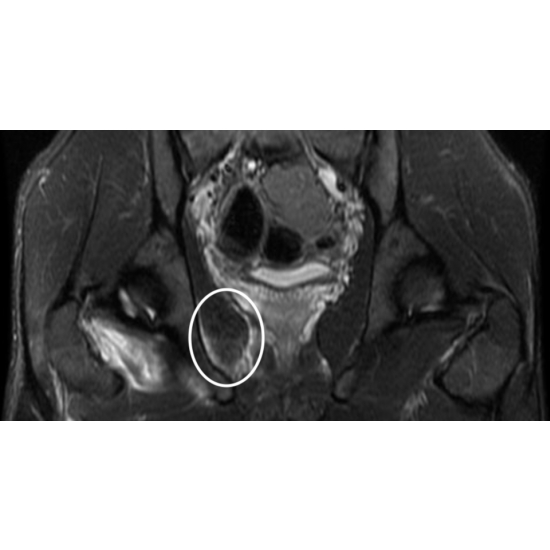

| Get A Kick Out Of This: National Women's Soccer Goalie And Division L Football Punter With Hip Pain - Page #3 | |||